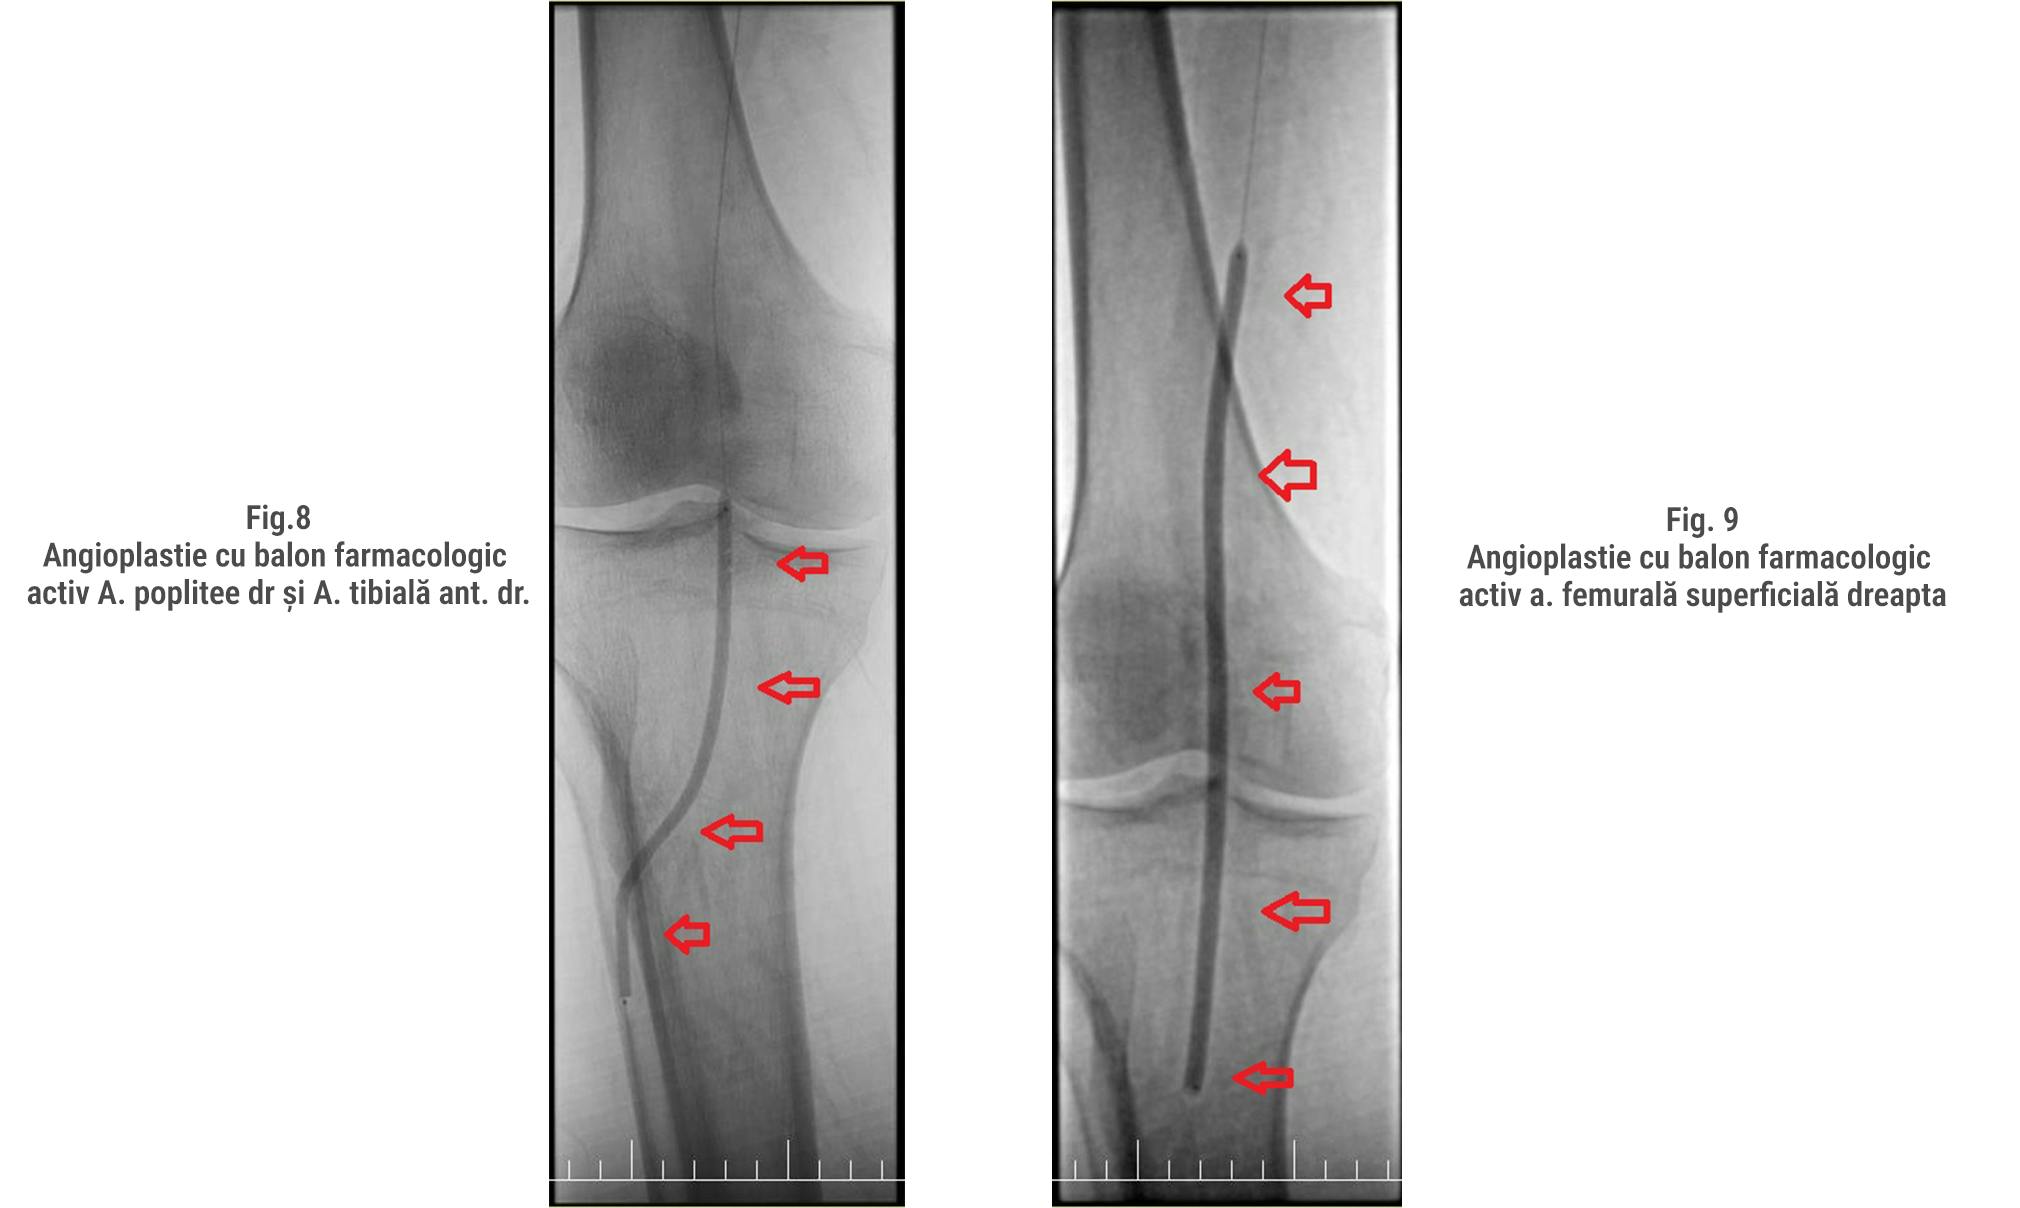

Angioplastia cu balon (Fig. 8/9) a fost utilizată pentru a dilata arterele blocate, folosind baloane farmacologic active care eliberează medicamente menite să prevină reocluzia. De asemenea, a fost administrată heparină pentru a preveni formarea cheagurilor de sânge în timpul procedurii.

Procedura CTO (Chronic Total Occlusion) reprezintă o tehnică avansată utilizată pentru tratarea arterelor complet blocate. În acest caz, s-a utilizat un ghid special și un microcateter pentru a traversa zona blocată. Echipa medicală a realizat dilatarea succesivă a arterelor femurale superficiale, poplitee și tibiale anterioare folosind baloane de diverse dimensiuni și presiuni. Această procedură complexă a necesitat utilizarea unor echipamente avansate și o coordonare precisă pentru a obține rezultate optime. (Fig. 6,7)